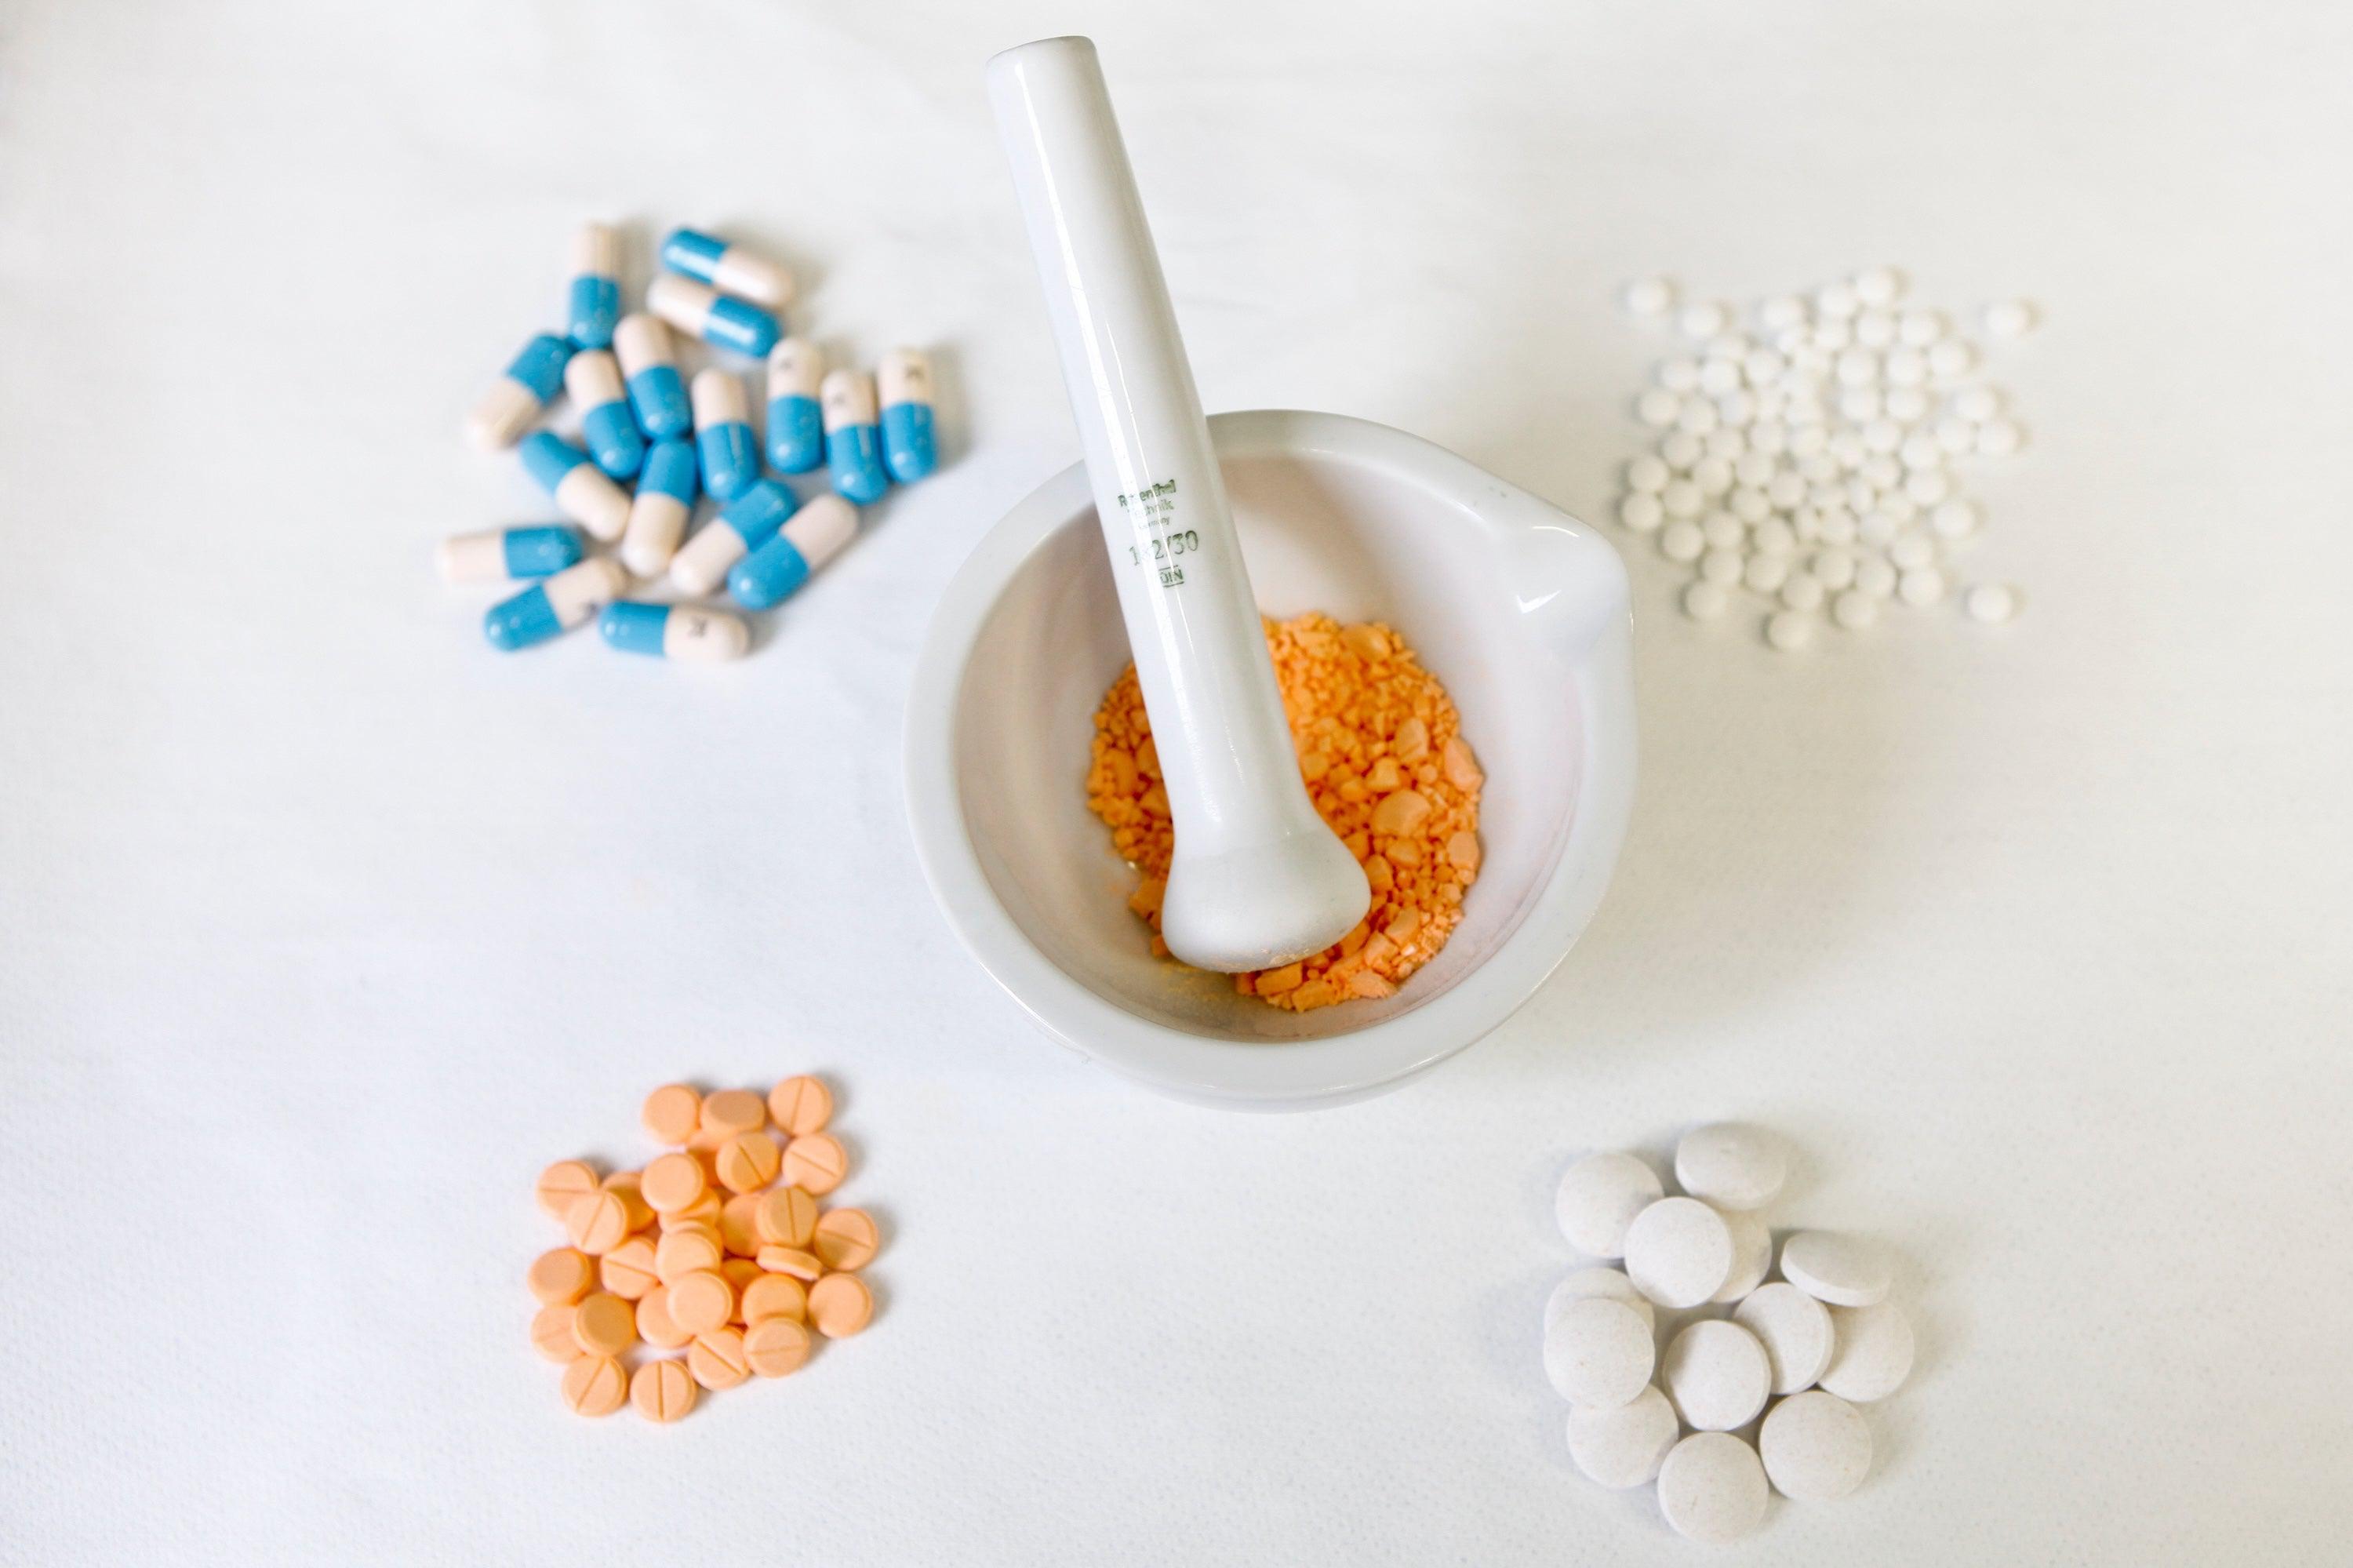

FDA wants to make more drugs available over the counter, but experts have raised safety concerns

FDA希望让更多药物在柜台上出售,但专家们提出了安全隐患的担忧

FDA wants to make more drugs available over the counter, but experts have raised safety concerns

FDA希望让更多药物在柜台上出售,但专家们提出了安全隐患的担忧

2026-02-20

1089词 困难

Why the FDA is cracking down on compound GLP-1 drugs for weight loss

FDA为何对复合GLP-1减肥药进行打击

Why the FDA is cracking down on compound GLP-1 drugs for weight loss

FDA为何对复合GLP-1减肥药进行打击

2026-02-18

1375词 困难